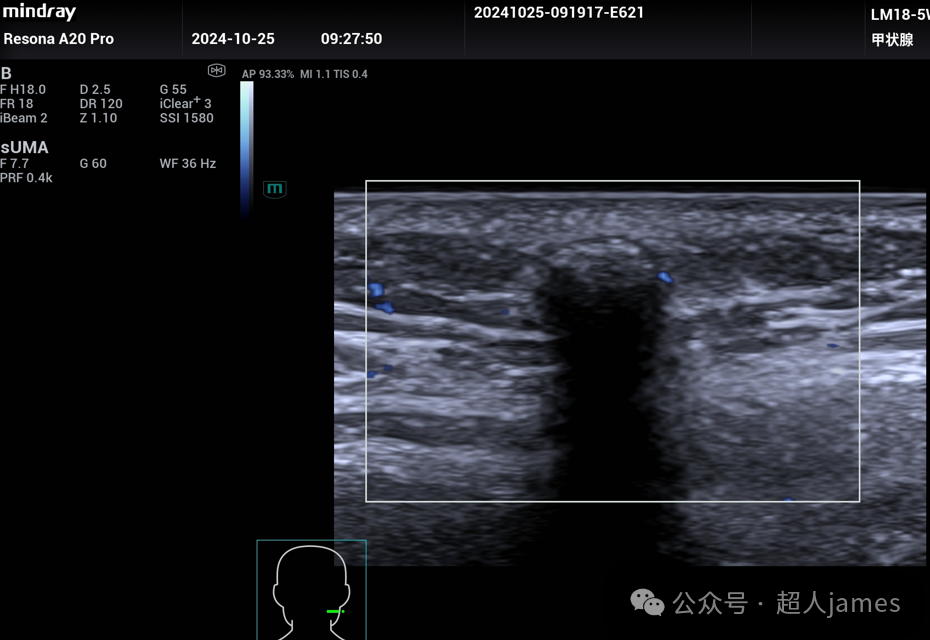

毛姆质瘤,又称钙化性上皮瘤,因此,其最大的特征就是在超声图像上往往表现为皮下以钙化为特征的包块。毛姆质瘤是来源于毛囊毛基质细胞的良性肿瘤,各年龄都可能发生,更常发生在儿童和青少年,单发多见,但也可以多发,常发生于头颈部。